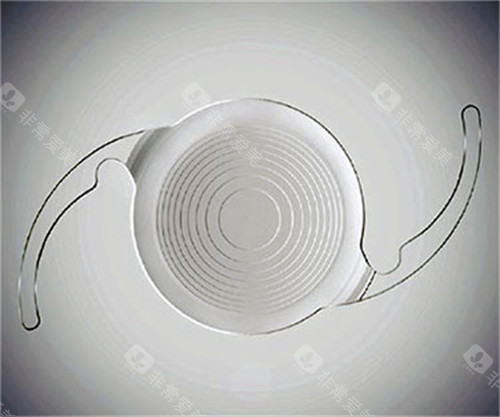

2. 国产晶体:从“追赶”到“并跑”

近年来,国产晶体在材料研发上进步显著。爱博诺德的非球面人工晶体采用国产疏水性丙烯酸酯,通过优化表面处理工艺,有效减少球差,成像质量已接近进口同类产品;天仁的折叠式晶体则以“超薄设计”为亮点,植入时切口更小,术后修养更快。

部分国产高端晶体甚至开始尝试“抗沉积涂层”技术,进一步降低术后炎症反应。